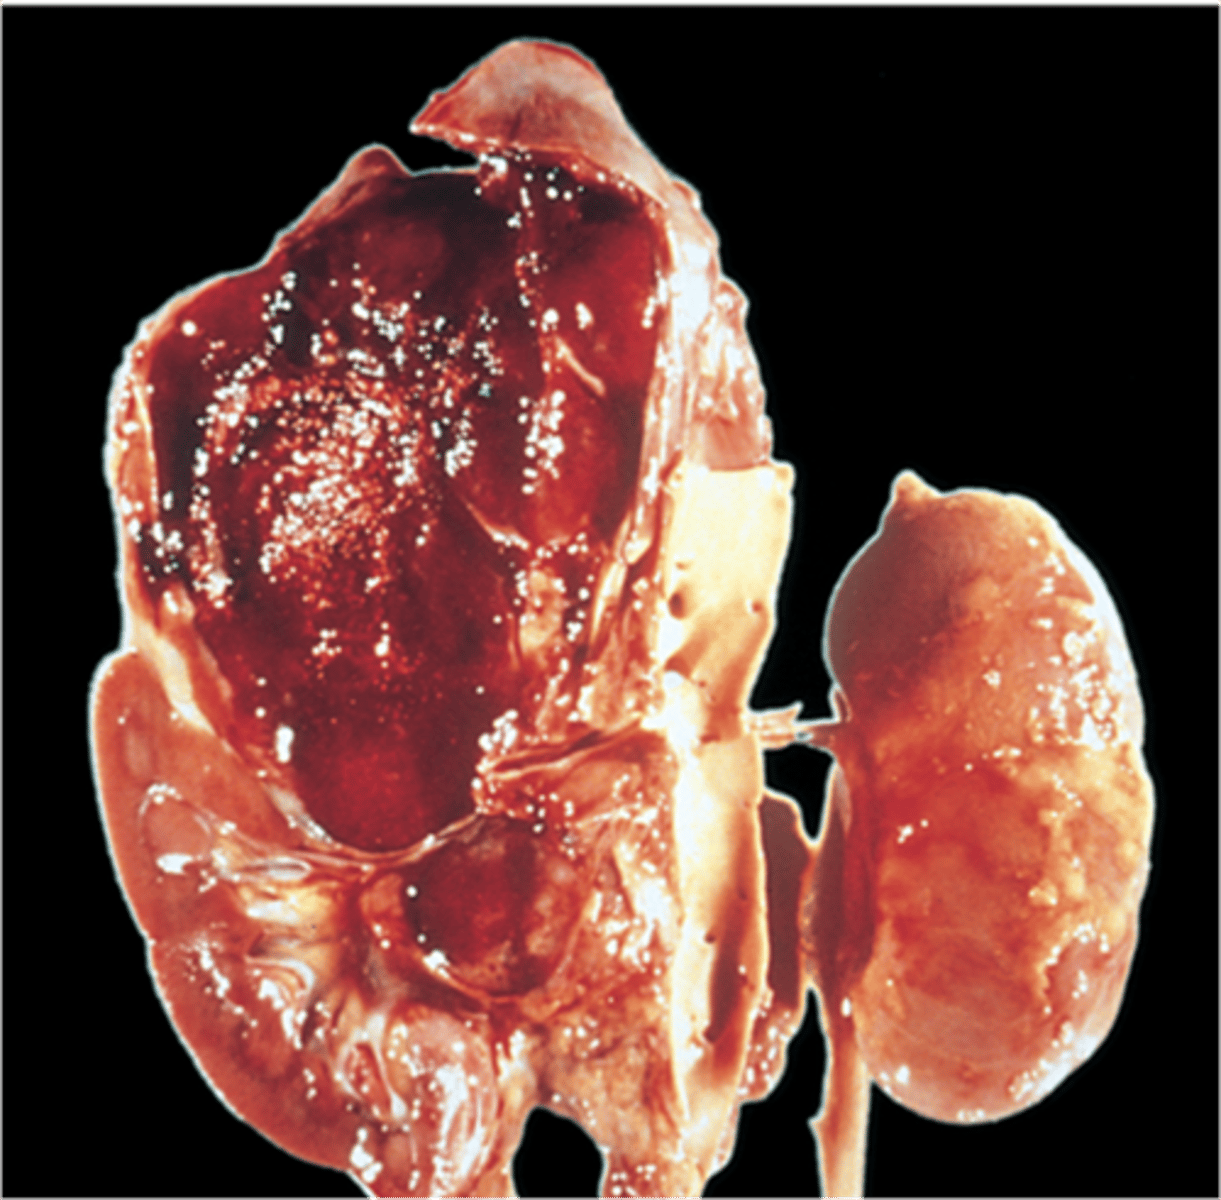

Waterhouse-Friderichsen syndrome

Pathology?